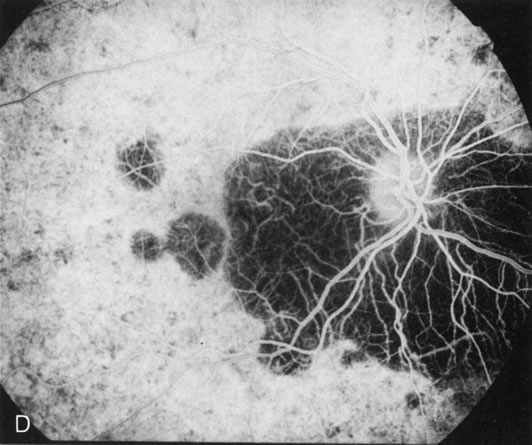

Generalized choroidal dystrophy is usually noted in middle-aged mildly symptomatic individuals who show a predominantly peripapillary or pericentral distribution of choroidal atrophy. Gradually, over the years these areas enlarge to eventually involve the entire retina. These changes are vividly seen on FA (Fig. 6).

Fig. 6. Generalized choroidal dystrophy. This 65-year-old woman gradually developed enlarging, progressive areas of choroidal atrophy over a 20-year period. When initially seen, the abnormalities were confined to the peripapillary and macular region (A,B). In a recent examination, the generalized choroidal atrophy is vividly demonstrated on angiography (C–F).